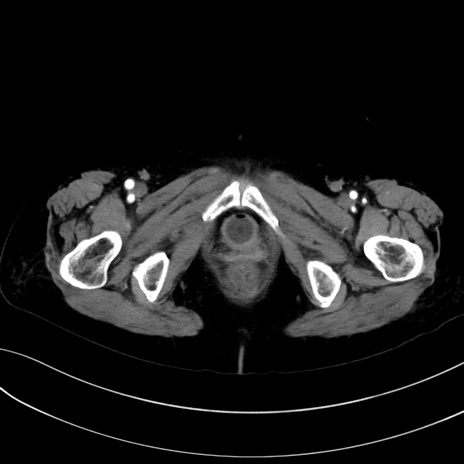

症例13 CT(横断像)1日半後